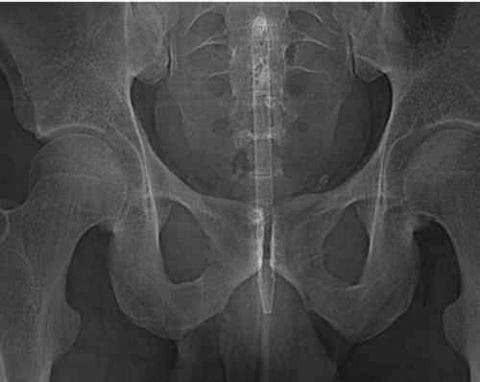

​↓这个的也搞笑圆珠笔怎么进去的啊?

看X光下那些意外进入身体的异物!个个奇葩搞笑